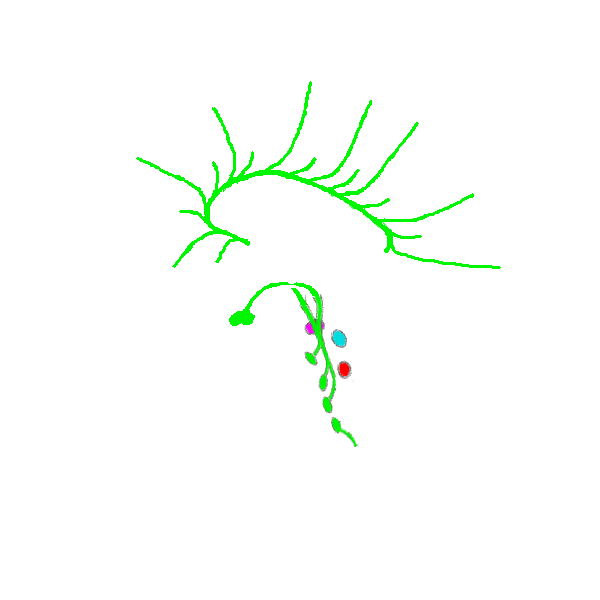

In dit systeem (schematisch weergegeven) is de volgorde van binnen naar buiten: global pallidus (binnen en buiten), putamen, caudate nucleus (de kern met de staart), amygdala en nucleus accumbens (links).

De caudate nucleus is vermoedelijk het centrale orgaan dat de analyses doet - het is net als de hippocampus (de cognitieve analysator) omgeven door hersenvloeistof (net als CPU en GPU in een computer).

De negatieve uitkomsten ("Gevaar!", en dergelijke) gaan naar de amygdala, de positieve naar de nucleus accumbens, en van deze twee naar de neurotransmitterbronnen in de hersenstam.

Het verschil met de analyse gedaan in de hersenstam is dat de laatste bijna puur van de aan/uit-soort is (zoals schakelaars), terwijl de basale ganglia meer werken als een analoge computer en veel genuanceerder kan analyseren.

Dit wordt verder aangevuld met kernen die om de basale ganglia heen liggen, en tezamen met emotieve systeem vormen. Dat zijnde dus de oordelen die de met het cognitieve brein waarnemende mens "emoties" noemt.

In dit systeem (schematisch weergegeven) is de volgorde van binnen naar buiten: global pallidus (binnen en buiten), putamen, caudate nucleus (de kern met de staart), amygdala en nucleus accumbens (links).

De caudate nucleus is vermoedelijk het centrale orgaan dat de analyses doet - het is net als de hippocampus (de cognitieve analysator) omgeven door hersenvloeistof (net als CPU en GPU in een computer).

De negatieve uitkomsten ("Gevaar!", en dergelijke) gaan naar de amygdala, de positieve naar de nucleus accumbens, en van deze twee naar de neurotransmitterbronnen in de hersenstam.

Het verschil met de analyse gedaan in de hersenstam is dat de laatste bijna puur van de aan/uit-soort is (zoals schakelaars), terwijl de basale ganglia meer werken als een analoge computer en veel genuanceerder kan analyseren.

Dit wordt verder aangevuld met kernen die om de basale ganglia heen liggen, en tezamen met emotieve systeem vormen. Dat zijnde dus de oordelen die de met het cognitieve brein waarnemende mens "emoties" noemt.

Ze bestaat op zich weer uit meerdere kernen gescheiden door bundels verbindingen (de witte strepen), zie de linkse, ietwat gedraaid:

Zoals die kernen in de hersenstam (vermoedelijk) gebruik maken van het neurale netwerk van de reticuliere formatie, maakt de thalamus (vermoedelijk) ook gebruik van een neuraal netwerk. En omdat de thalamus de eerste kern buiten de "buis" van de hersenstam is, kan dat neurale netwerk ook buiten die buis - dat is natuurlijk de cortex die eromheen ligt. De volgende illustratie toont schematisch de verbindingen tussen de twee: